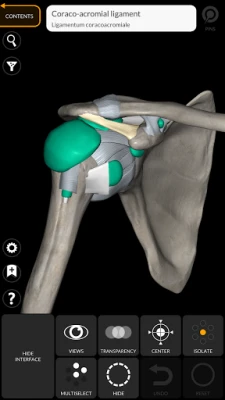

"Anatomy 3D Atlas" allows you to study human anatomy in an easy and interactive way.

Through a simple and intuitive interface it is possible to observe every anatomical structure from any angle.

The anatomical 3D models are particularly detailed and with textures up to 4k resolution.

The subdivision by regions and the predefined views facilitate the observation and the study of single parts or groups of systems and the relationships between different organs.

ANATOMICAL 3D MODELS

• Musculoskeletal system

• Simple and intuitive interface

• Rotate and zoom each model in 3D space

• Option to hide or isolate single or multiple selected models

• Filter to hide or display each system

• Transparency function

"Anatomy 3D Atlas" allows you to study human anatomy in an easy and interactive way.

Through a simple and intuitive interface it is possible to observe every anatomical structure from any angle.

The anatomical 3D models are particularly detailed and with textures up to 4k resolution.

The subdivision by regions and the predefined views facilitate the observation and the study of single parts or groups of systems and the relationships between different organs.

• Simple and intuitive interface

• Rotate and zoom each model in 3D space

• Option to hide or isolate single or multiple selected models

• Filter to hide or display each system

• Transparency function